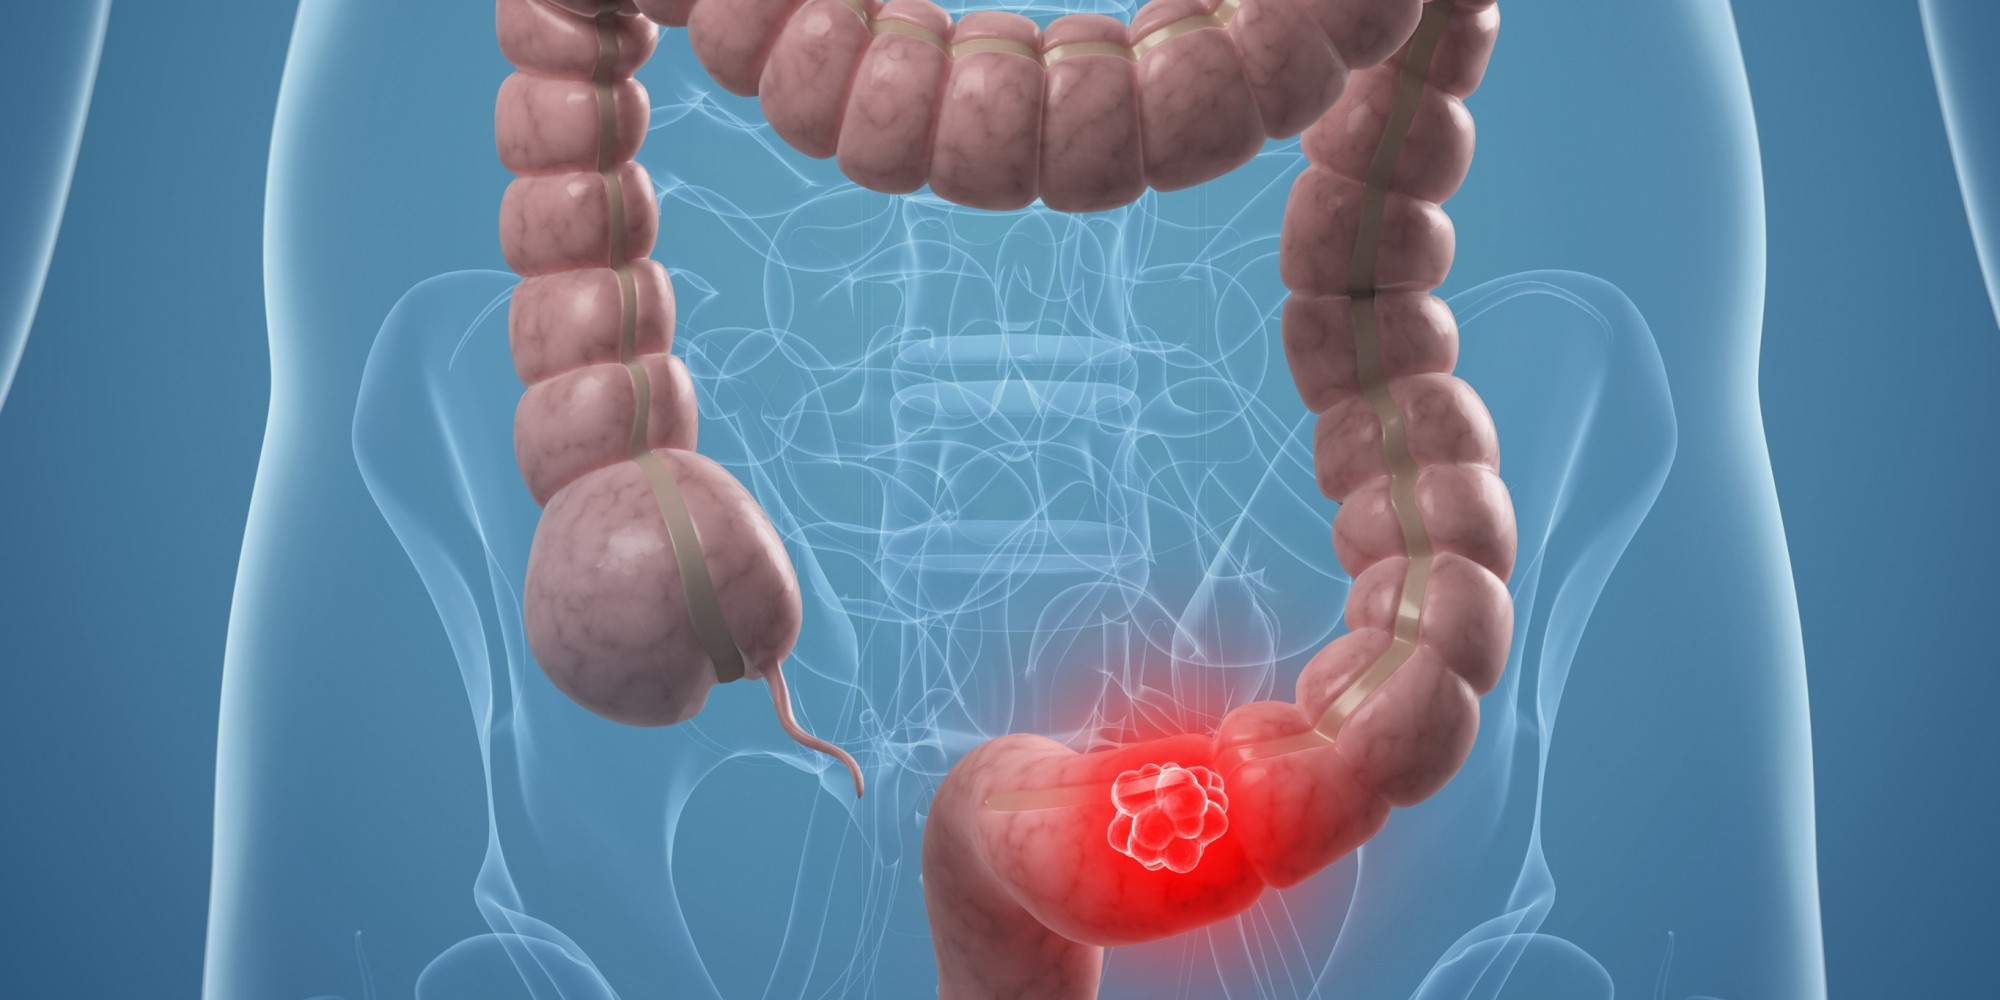

Η κατανάλωση δημητριακών ολικής αλέσεως μειώνει τον κίνδυνο εμφάνισης καρκίνου του παχέος εντέρου, ενώ τα χοτ-ντογκ, το μπέϊκον και τα άλλα κατεργασμένα κόκκινα κρέατα τον αυξάνουν, σύμφωνα με μια αμερικανική επιστημονική μελέτη.

Όσοι τρώνε περίπου τρεις μερίδες (90 γραμμάρια) δημητριακών ολικής αλέσεως τη μέρα, έχουν κατά μέσο όρο 17% μικρότερο κίνδυνο για καρκίνο του εντέρου.

Η μελέτη επιβεβαιώνει προηγούμενες έρευνες, σύμφωνα με τις οποίες οι τροφές που περιέχουν φυτικές ίνες, μειώνουν τον κίνδυνο για τη συγκεκριμένη μορφή καρκίνου.

Από την άλλη, ο κίνδυνος για καρκίνο του παχέος εντέρου αυξάνεται, εκτός από την τακτική κατανάλωση κατεργασμένων κρεάτων, όταν κανείς:

- τρώει πολύ κόκκινο κρέας όπως μοσχάρι ή χοιρινό (πάνω από μισό κιλό την εβδομάδα)

- είναι υπέρβαρος ή παχύσαρκος

- καταναλώνει καθημερινά πάνω από δύο αλκοολούχα ποτά (30 γραμμάρια), όπως κρασί ή μπίρα

Οι ερευνητές, με επικεφαλής τον καθηγητή διατροφολογίας και επιδημιολογίας Έντουαρντ Τζιοβανούτσι της Σχολής Δημόσιας Υγείας του Πανεπιστημίου Χάρβαρντ, που έκαναν τη σχετική μελέτη για λογαριασμό του Αμερικανικού Ινστιτούτου Ερευνών για τον Καρκίνο (AICR) και του Παγκόσμιου Ταμείου Ερευνών για τον Καρκίνο (WCRF), αξιολόγησαν όλα τα έως τώρα δεδομένα διεθνώς για τη σχέση διατροφής-καρκίνου του παχέος εντέρου, λαμβάνοντας υπόψη τους 99 έρευνες, που αφορούσαν περίπου 29 εκατομμύρια ανθρώπους.

Η μελέτη επισημαίνει ότι όσα περισσότερα πλήρη δημητριακά (ψωμί, ρύζι κ.α.) τρώει κανείς, τόσο μειώνεται ο κίνδυνος. Εξίσου προστατευτικά για το παχύ έντερο δρα και η σωματική άσκηση.

«Ο καρκίνος του παχέος εντέρου είναι ένας από τους συχνότερους καρκίνους και η νέα μελέτη δείχνει ότι υπάρχουν πολλά που οι άνθρωποι μπορούν να κάνουν, για να μειώσουν δραστικά τον κίνδυνο. Η διατροφή και ο τρόπος ζωής παίζουν καθοριστικό ρόλο στο συγκεκριμένο καρκίνο», δήλωσε ο Τζιοβανούτσι.

Όπως είπε, πρέπει κανείς «να διατηρεί κανονικό σωματικό βάρος, να ασκείται τακτικά, να περιορίσει την κατανάλωση επεξεργασμένου και κόκκινου κρέατος, να τρώει περισσότερα δημητριακά ολικής αλέσεως και ίνες, καθώς επίσης να μειώσει το αλκοόλ και να αποφεύγει το κάπνισμα ή να το κόψει τελείως».

Από την άλλη, σύμφωνα με τη νέα μελέτη, προς το παρόν δεν υπάρχουν αρκετά στοιχεία που να επιβεβαιώνουν ότι η μικρή κατανάλωση φρούτων και λαχανικών αυξάνει τον κίνδυνο καρκίνου του παχέος εντέρου.

Υπάρχουν πάντως ενδείξεις ότι αν κανείς τρώει λιγότερα από 100 γραμμάρια φρούτων και 100 γραμμάρια λαχανικών τη μέρα, ο κίνδυνος μπορεί να αυξηθεί.

Επίσης συσσωρεύονται οι ενδείξεις ότι μειώνεται ο κίνδυνος, αν κανείς τρώει πολλά ψάρια και τρόφιμα πλούσια σε βιταμίνη C, όπως πορτοκάλια, φράουλες και σπανάκι.